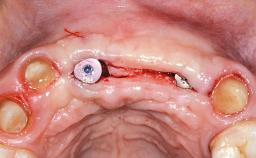

Replacement of Teeth 12 and 13 with Tissue-Level Implants

In 2001, a 48-year-old woman presented at a dental clinic with a failing fixed partial denture spanning from teeth 13 to 21. She was experiencing pain upon function, tenderness to palpation facial to tooth 13, and severe mobility of the prosthesis. Radiographic and clinical assessment revealed a subcrestal fracture of tooth 13, making its restoration unlikely. It was determined by the clinician that the tooth needed to be extracted prior to proceeding any further with dental care. After the extraction, the patient lost confidence in the progression of her treatment and sought consultation at the Center for Implant Dentistry. At her consultation visit in our clinic, an extra- and intraoral clinical examination revealed a medium lip line at full smile and an edentulous area spanning from 13 to 12 with both vertical and horizontal deficits in hard and soft tissue.